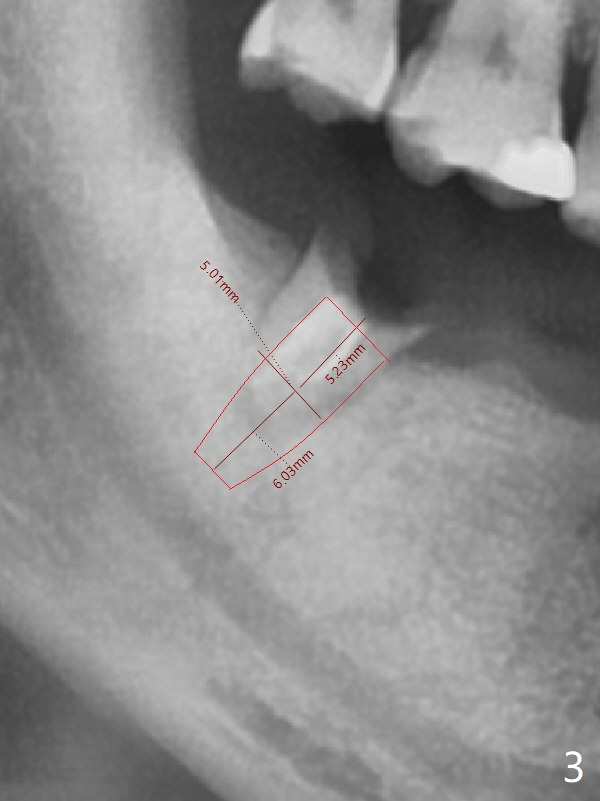

My question is have you measured the how much remaining bones are left at the extraction socket. How much bone depth is left after the root extraction? Do you think the implant could get enough fixation after the extraction? Jennifer It is a good question. As today's CT indicates (07/30/2018), there is ~ 3 mm bone for primary stability with ~ 1 mm clearance (Fig.3-6). Because of the tapered implant, ~5 mm of the implant will be able to contact the native bone if the implant is lingually placed (Fig.6). If you feel it too much a risk, still make a guide for #31 so that an anchor pin can be placed at #31 residual roots for fixation (a new idea?). Make sure that the distal portion of the guide contacts the #31 residual root stump for stability, which is superior to a guide resting on the soft tissue. I have had experience placing implants free hand in this situation. The guide will be great help. I will use judgment in surgery. The worst scenario is socket preservation. Thanks for consideration and design.